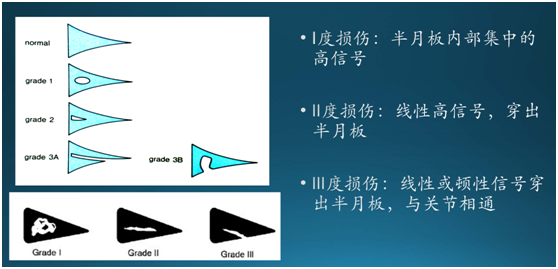

综上所述,如果您怀疑你的半月板损伤了,请到正规的医院让专业的膝关节外科医生检查,结合受伤机制、疼痛特点和体格检查来判断,由于现在都需要客观证据,因此很多患者需要做磁共振(MRI)检查。

半月板损伤是否需要手术治疗跟早期还是晚期损伤并没有直接联系,主要看损伤的类型和程度。一般磁共振会给我们明确的半月板损伤类型和程度。因为半月板是个三维结构,所以用衣服打比方还不够适合,用墙壁更加合适。

磁共振I、II度半月板损伤:以后我们称之为半月板损伤,相当于墙壁外观和功能良好,仅仅是墙壁内部有洞,这个洞并没有累计墙壁表面和影响强的结构。这种损伤往往可以保守治疗,半月板会疤痕修复。当然,这留下了隐患,下次受伤这个洞又会扩大。

磁共振III、IV度半月板损伤:以后我们称之为半月板破裂,相当于墙壁裂开或者起不到正常的支撑作用了,这种损伤无论是在早期或者晚期,一旦发现要尽早手术,否则随着您的活动和运动,就像前面的衣服破口一样,会越来越大。同时破裂的半月板会把关节软骨磨坏,(您可以想象光滑的机器表面有一些沙子或者小石头),也就是医生所说的骨性关节炎,请注意,目前医学对关节软骨损伤和骨性关节炎并没有好办法,除了关节置换大部分的治疗方式也就60-70%左右的病人疗效满意,你能保证您不是那30%吗?